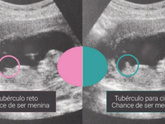

Это девочка, наклон в низ, у вальчика в верх

Что видно? На этом сроке если вы не знали и у девочек и у мальчиков половой бугорок одинаковый, только наклон разный

Мне тоже кажется, что это девочка, у мальчиков угол больше вроде.

Вот что выдаёт интернет ?

У нас эта кость была не к низу как у вас и более вверх, сказали мальчик, так и получилось